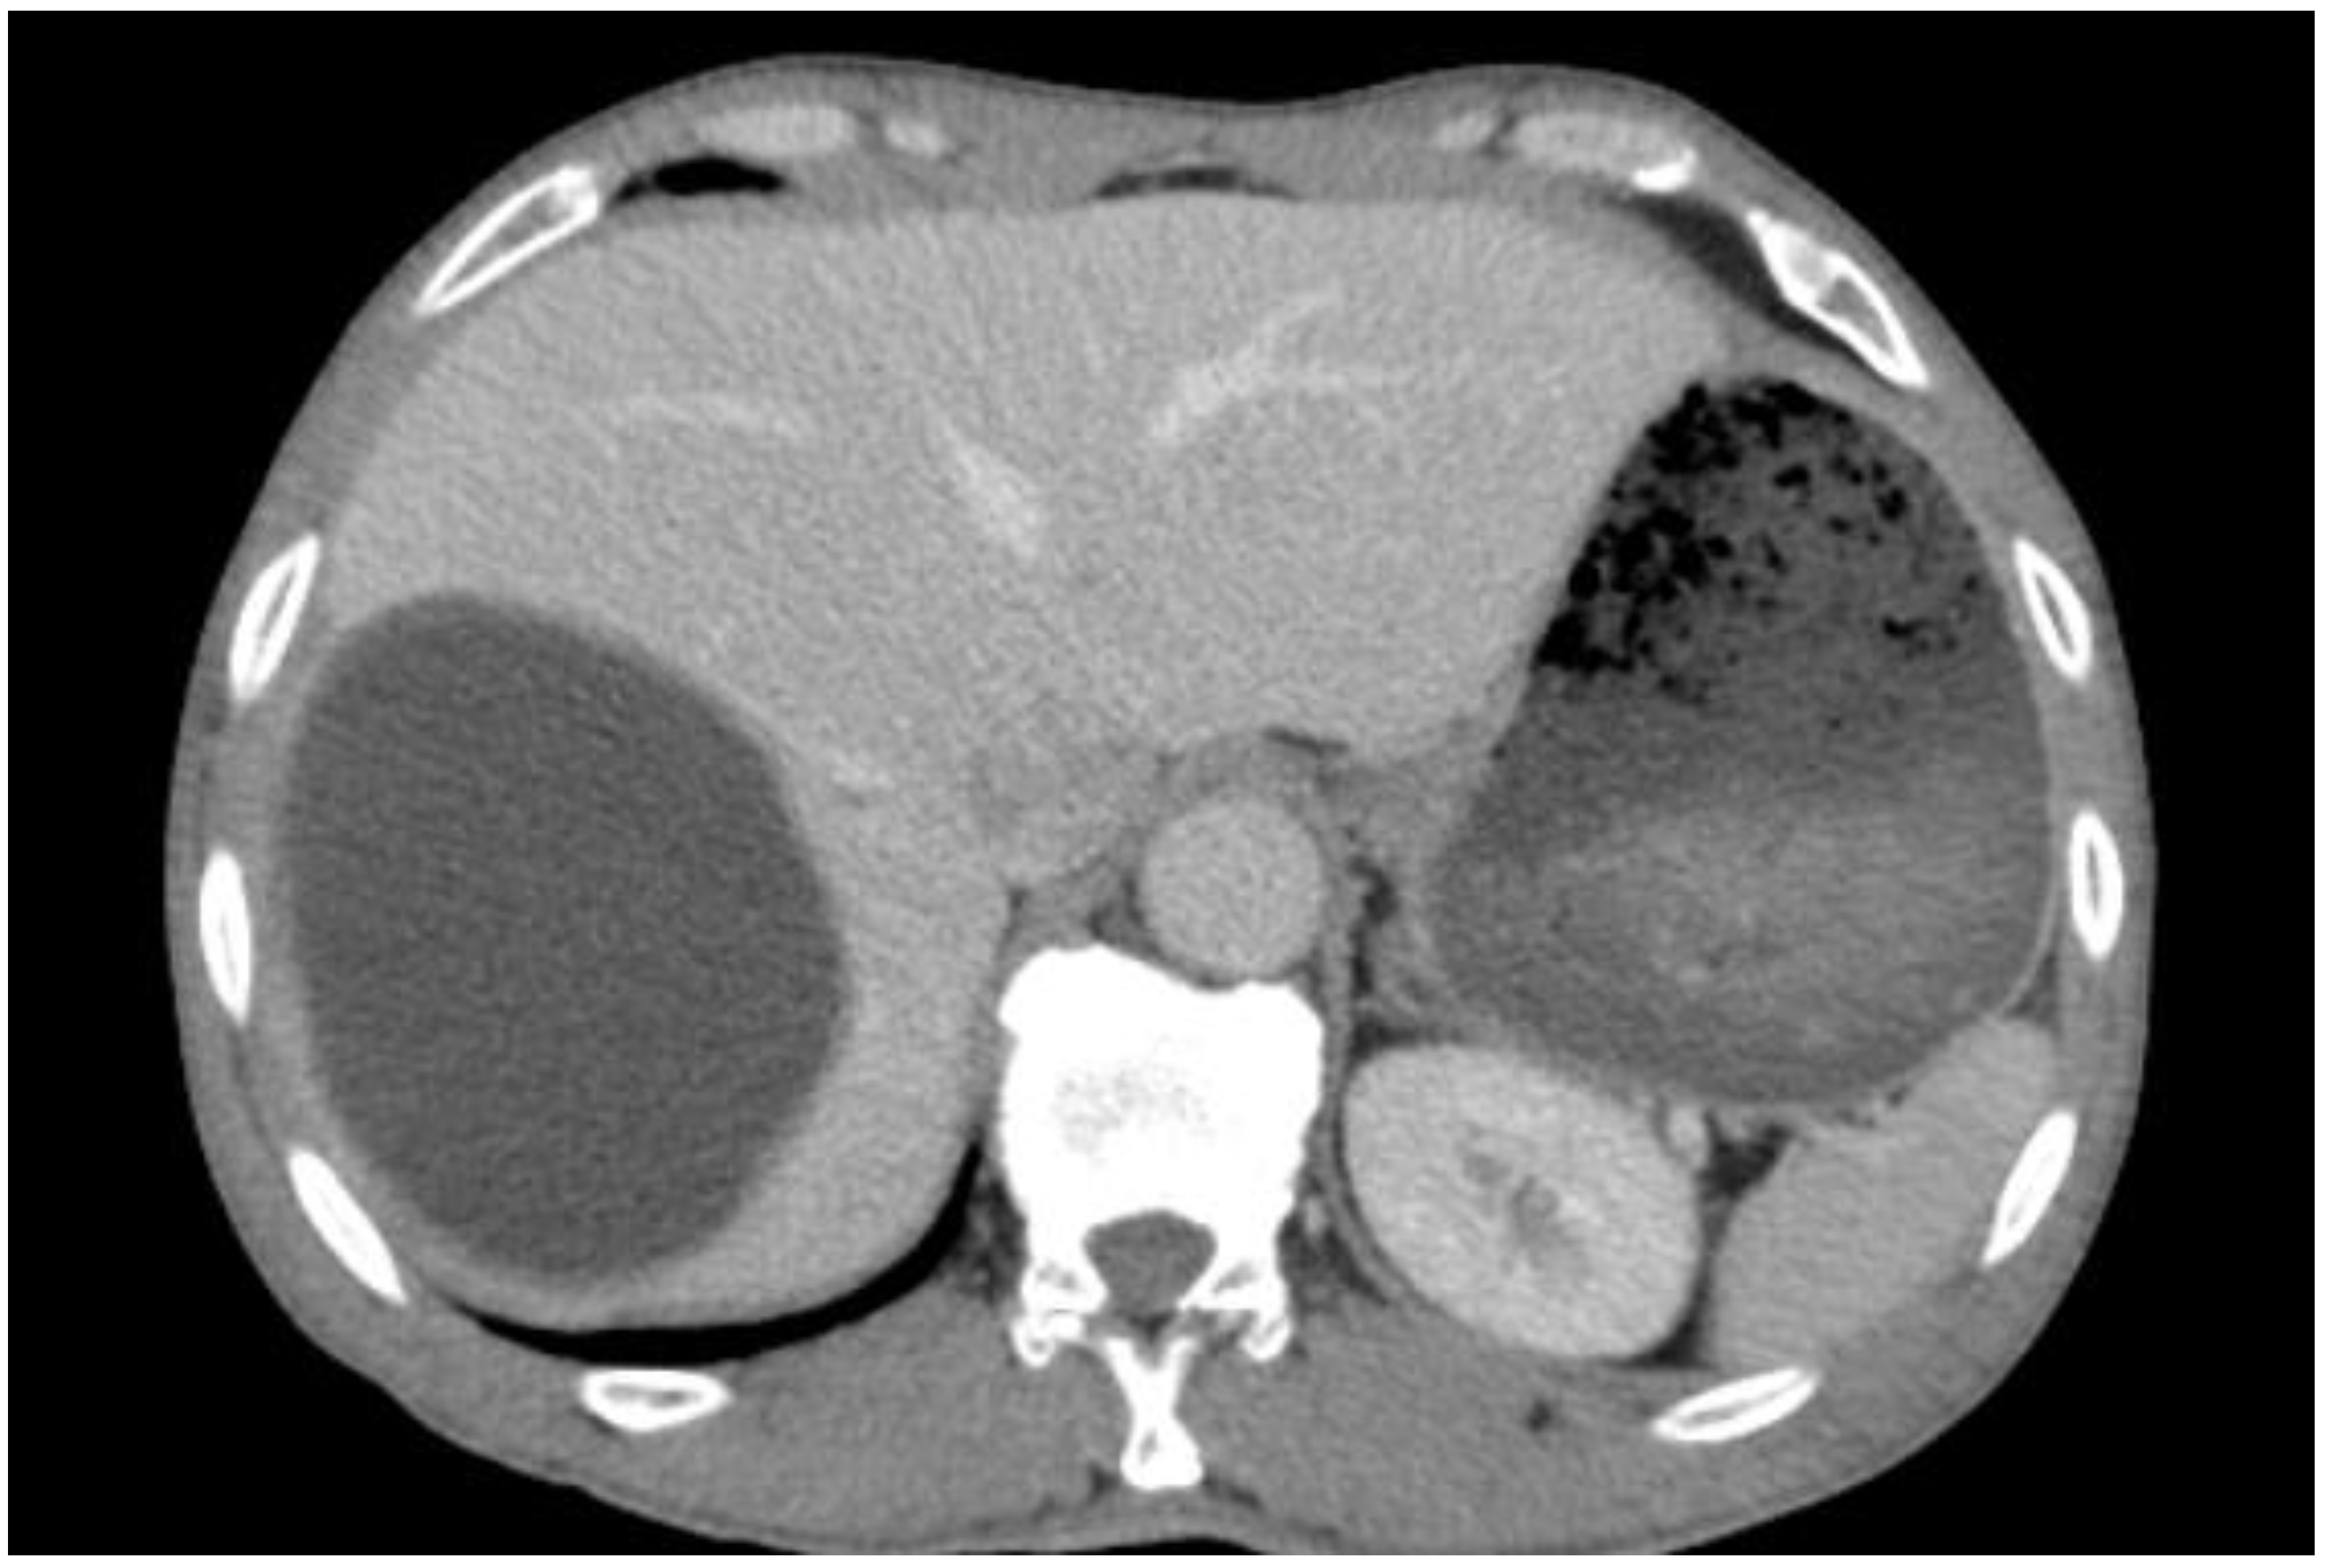

5.1. Hydatid Cysts of the Liver